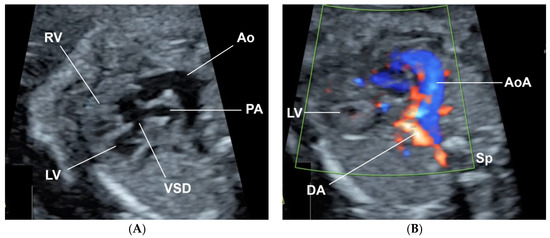

At 38+4 weeks, she had vaginal delivery, giving birth to a female baby, with birthweight of 2580 g (9th percentile of WHO growth chart); APGAR score 8 and 9 at 1 and 5 min, respectively, with excessive secretion in both nostrils. The left ear showed a clipped off helix (Figure 5). Otoscopic examination showed bilateral ear canal stenosis with cerumen. Funduscopic examination revealed optic disc coloboma on the right eye and choroidal coloboma on the left eye (Figure 6). Abdominal ultrasound revealed mal-rotation of both kidneys but with normal size and echogenicity of the renal parenchyma; no dilatation of the pelvicalyceal system was observed. Neonatal echocardiography confirmed the prenatal findings. Because of inability to pass nasogastric tube, bilateral choanal atresia was suspected and confirmed by CT scans of the head (Figure 7).

Figure 7. Bilateral bony choanal atresia: narrowing of bilateral posterior choanae, measuring about 0.29 and 0.22 cm on right and left sides, respectively.